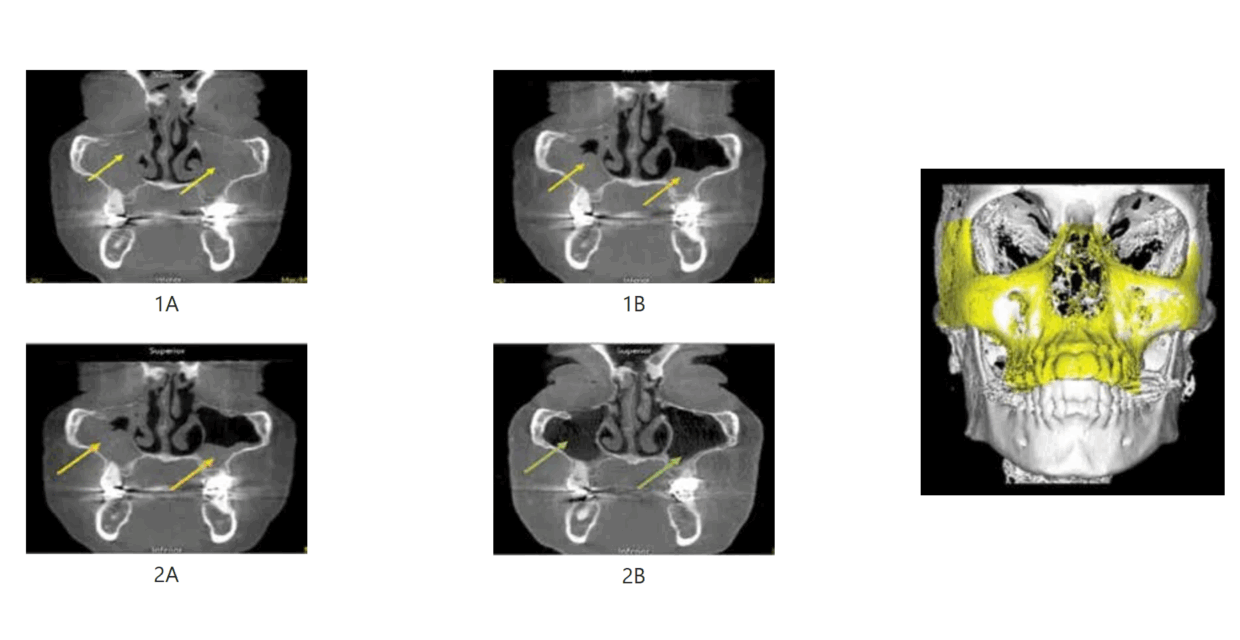

Resolution of Chronic Rhinosinusitis with Polyposis following Maxillary Morphogenic Functional Appliance

Wednesday, 01 March 2023

Published March, 2023Co-authored by Theodore R Belfor, DDS, FPFA, FIADFE; David E. McCarty, MD, FAASM and Scott Holyoak, DDS Chronic Rhinosinusitis (CRS) is an inflammation of the paranasal sinuses lasting longer than 12 weeks and accompanied by pathologic symptoms, such as difficulty breathing, nasal congestion, and facial pain/pressure. Symptoms of nasal obstruction, nasal discharge, and